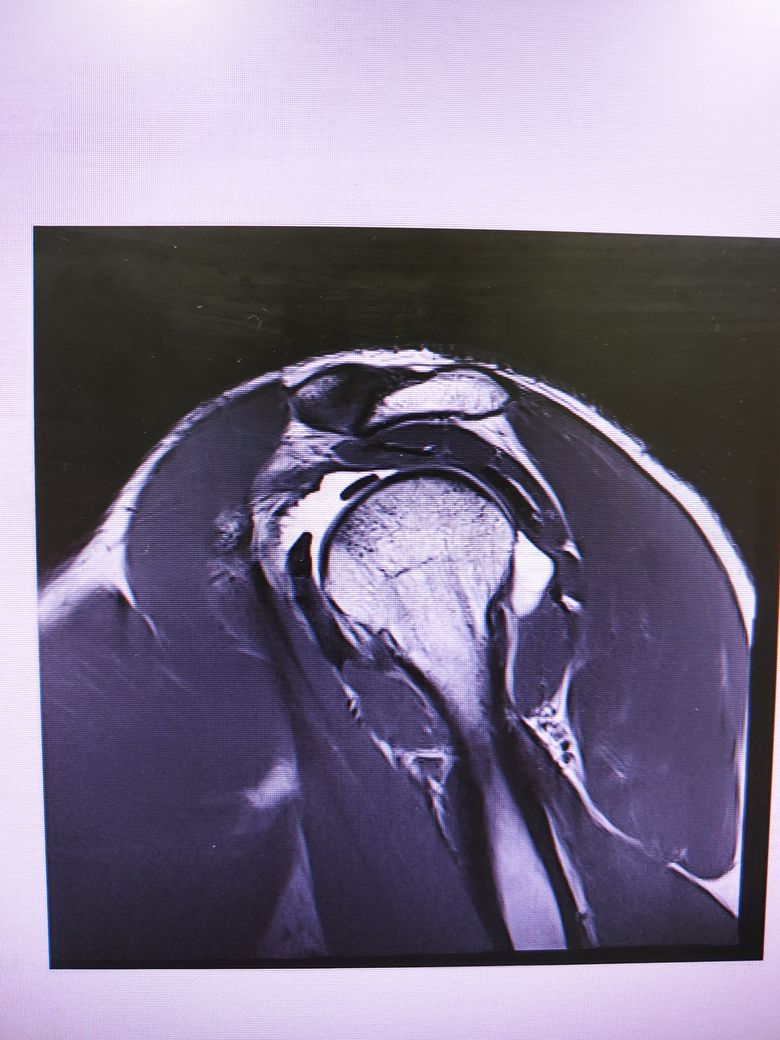

팔이 잡아당겨지는 사고 이후 통증이 지속되어

조영제 투입 후 mri 촬영을 하였습니다.

진단명은 상부관절와순파열(슬랩)이며

헬스와 같은 운동을 계속 하려면 수술이 필요하다 하였습니다.

슬랩이 맞나요? 맞다면 파열 진행 정도는 어느정도인지..

궁금합니다..최대한 사진 많이 올립니다 감사합니다..